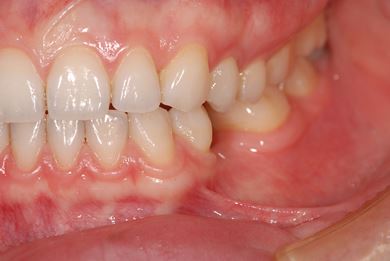

| 性別/年齢 | 女性 / 29歳 | ||||||||||||||||||||||||||||||||

| 主訴 | インプラント治療と、親知らずの抜歯の相談。なるべく安価で、短期間で終了して欲しい。 | ||||||||||||||||||||||||||||||||

| 治療方針 | 欠損部分をインプラント治療にて、機能的・審美的回復を行う。 | ||||||||||||||||||||||||||||||||

| 治療内容 | インプラント1本、メタルボンドセラミッククラウン1本 | ||||||||||||||||||||||||||||||||

| 総治療費 | 252,000円 | ||||||||||||||||||||||||||||||||

| 治療期間 | 11ヶ月 |